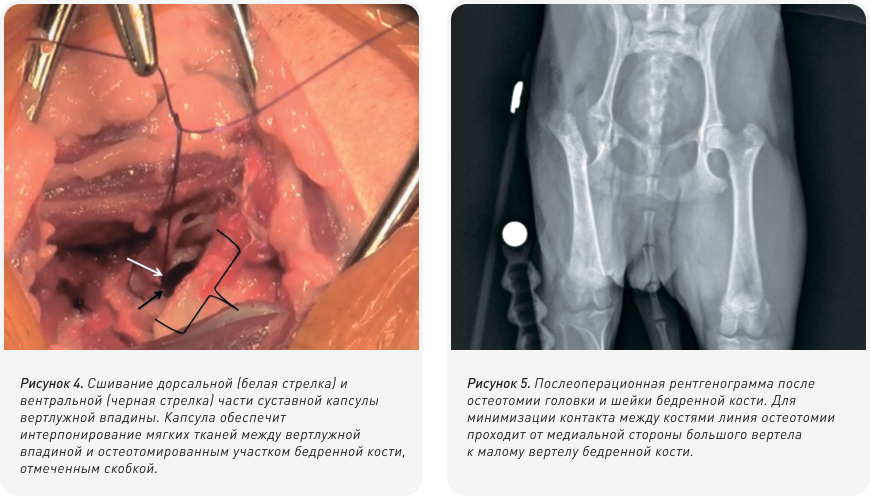

При обнаружении таковых, костные шпоры можно удалить с помощью костных кусачек, после чего участок сглаживается рашпилем. Рану следует обильно промыть для удаления оставшихся фрагментов и костной пыли. Следует проверить комплекс движений ложного сустава, чтобы убедиться в отсутствии существенного контакта между костями. Суставная капсула с дорсального края вертлужной впадины может затем быть ушита с вентральной стороной вертлужной впадины для интерпозиции мягких тканей между вертлужной впадиной и оставшейся частью бедренной кости (Рис. 4). Для подтверждения того, что головка и шейка бедренной кости были иссечены полностью, проводится послеоперационная рентгенография (Рис. 5).

Для проведения остеотомии может применяться небольшая электропила, пила Джильи или остеотом с молотком; в некоторых случаях кость может оказаться очень мягкой или даже сломанной, и в такой ситуации для удаления оставшейся части головки бедренной кости возможно применение костных кусачек. Для обеспечения правильной антеверсии головки и шейки бедренной кости бедро должно быть адекватно повернуто кнаружи. Этого можно достичь путем фиксации скакательного сустава (пяточной кости — tuber calcis) к латеральной стенке грудной клетки. Остеотомия проводится от основания большого вертела к третьему вертелу бедренной кости (Рис. 3). После резекции головки и шейки бедренной кости участок резекции следует пальпировать для выявления каких-либо острых фрагментов на оставшейся кости, обычно на каудомедиальной стороне остеотомированного участка бедренной кости.